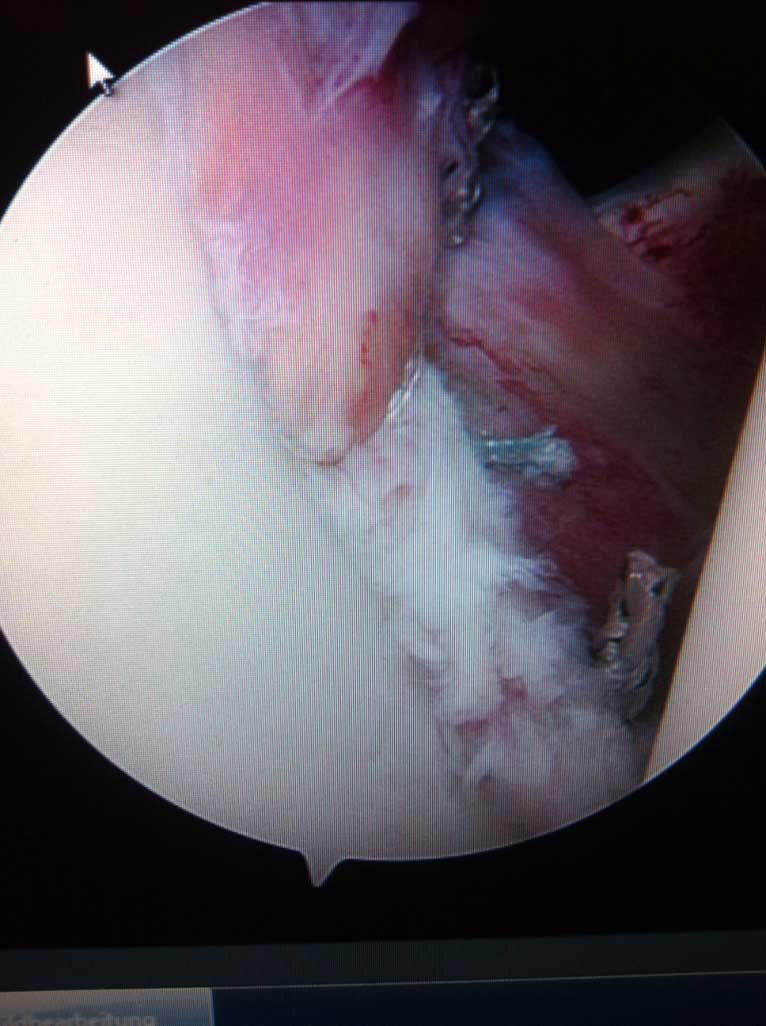

Je nach Alter, Verletzungsmuster, Anzahl der Luxationsereingnisse und weiteren Faktoren, wird eine schulterstabilisierende Operation indiziert und empfohlen. Diese führen wir ebenfalls ausschliesslich arthroskopisch

(Schüsselloch Operation) durch. Innerhalb von 15 - 30 min wird dabei der knorpelige Ring (s.g. Labrum) auf den knöchernen Pfannenrand mit speziellen Anker und Fäden wieder zurück befestigt.

Die Nachbehandlung richtet sich nach Schwergrad der operativ versorgten Verletzungen, beträgt allerdings in d.R. nicht länger als 8-10 Wochen, inkl. Rückkehr zu Kontaktsportarten binnen 12 Wochen nach Operation.